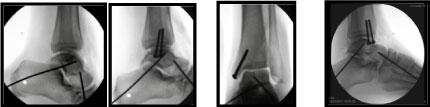

A K-wire each was inserted through the talo-calcaneal and talo-navicular joints under fluoroscopy to ensure stability. The medial malleolar fracture was stabilised with 2 partially threaded cancellous screws (Figure 7).

Figure 7: Intra-operative radiographs of K-wire stabilisation and Medial malleolar fixation. View Figure 7

Post-operative CT scans showed good reduction and alignment of the talus and medial malleolar fracture (Figure 8). Patient was followed up in clinic a week after discharge. Sutures were removed and wound healing was satisfactory. The cast was removed and patient was mobilised in air cast boot and crutches and he flew back to the USA after 2 weeks.

Figure 8: Post op CT scan showing anatomical reduction of the talus and internal fixation of medial malleolus. View Figure 8